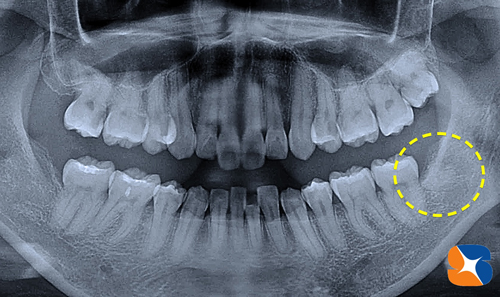

神戸市より30代の主婦。主訴は、「近くの歯医者で,この親知らずの抜歯は出来ないと言われた。大学病院を勧められたが、寝ながら(静脈麻酔鎮静法)抜歯出来るところを探していた。なかなか時間が取れないので、一気に左右両方の抜歯をして欲しい。」でした。

レントゲンの結果、右下:横向きの親知らず(向かって左)が、あご骨の中に深く埋もれている事が分かりました。また、左下:上向きの親知らず(向かって右)もなんとなく難しいのでは?と感じました。